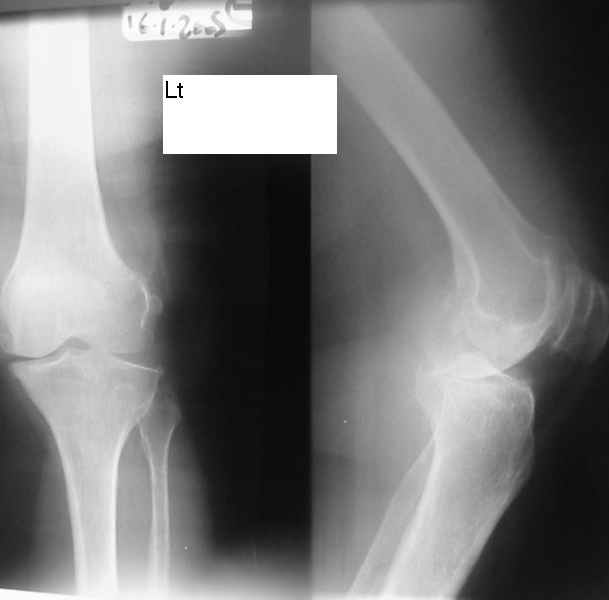

Dorogie Kollegy,Ko mne obratilas' bol'najia, ei 64 goda, ona stradaet ot dvuhstoronnego varusnogo gonoartroza, ei bila vipolnena Visokajia Ostotomjia goleny sprava 01.06.2004, zona osteotomii ne sroslas', plastina bila udalena 12.09.2004 (vidimo iz-za ee nestabilnosti), zona osteotomii tibia bila fixirovana 3-mjia shurupami. Seachas sylno bespokoyat boly v dvuh sustavah, hodit s trudom s pomoshyu Walker, a voobshe ona seachas na invalidnoi kolyaske. Podzkazite, pozhalusta, kak mozno ei pomoch' (snimky prilagayutsa)

1. I predpochel bi ego: Total Knee Arthroplasty. Nuzhen budet Revision ( Long stem) tibial Component.

2. Ne sovetuiu delat' geroicheskix postumkov v otnoshenii Non union. Tut est' mnogo problem, ved' esteotomia provedena ne pravili'no s tochki zrenia deformazii. Orientazia ploskosto kollennogo sustava xotia ne ploxa v sagital'noii ploskosti, no vo frontl'noi idet sil;noie otklonenie narozhu i vniz. A nam tida ne nado.